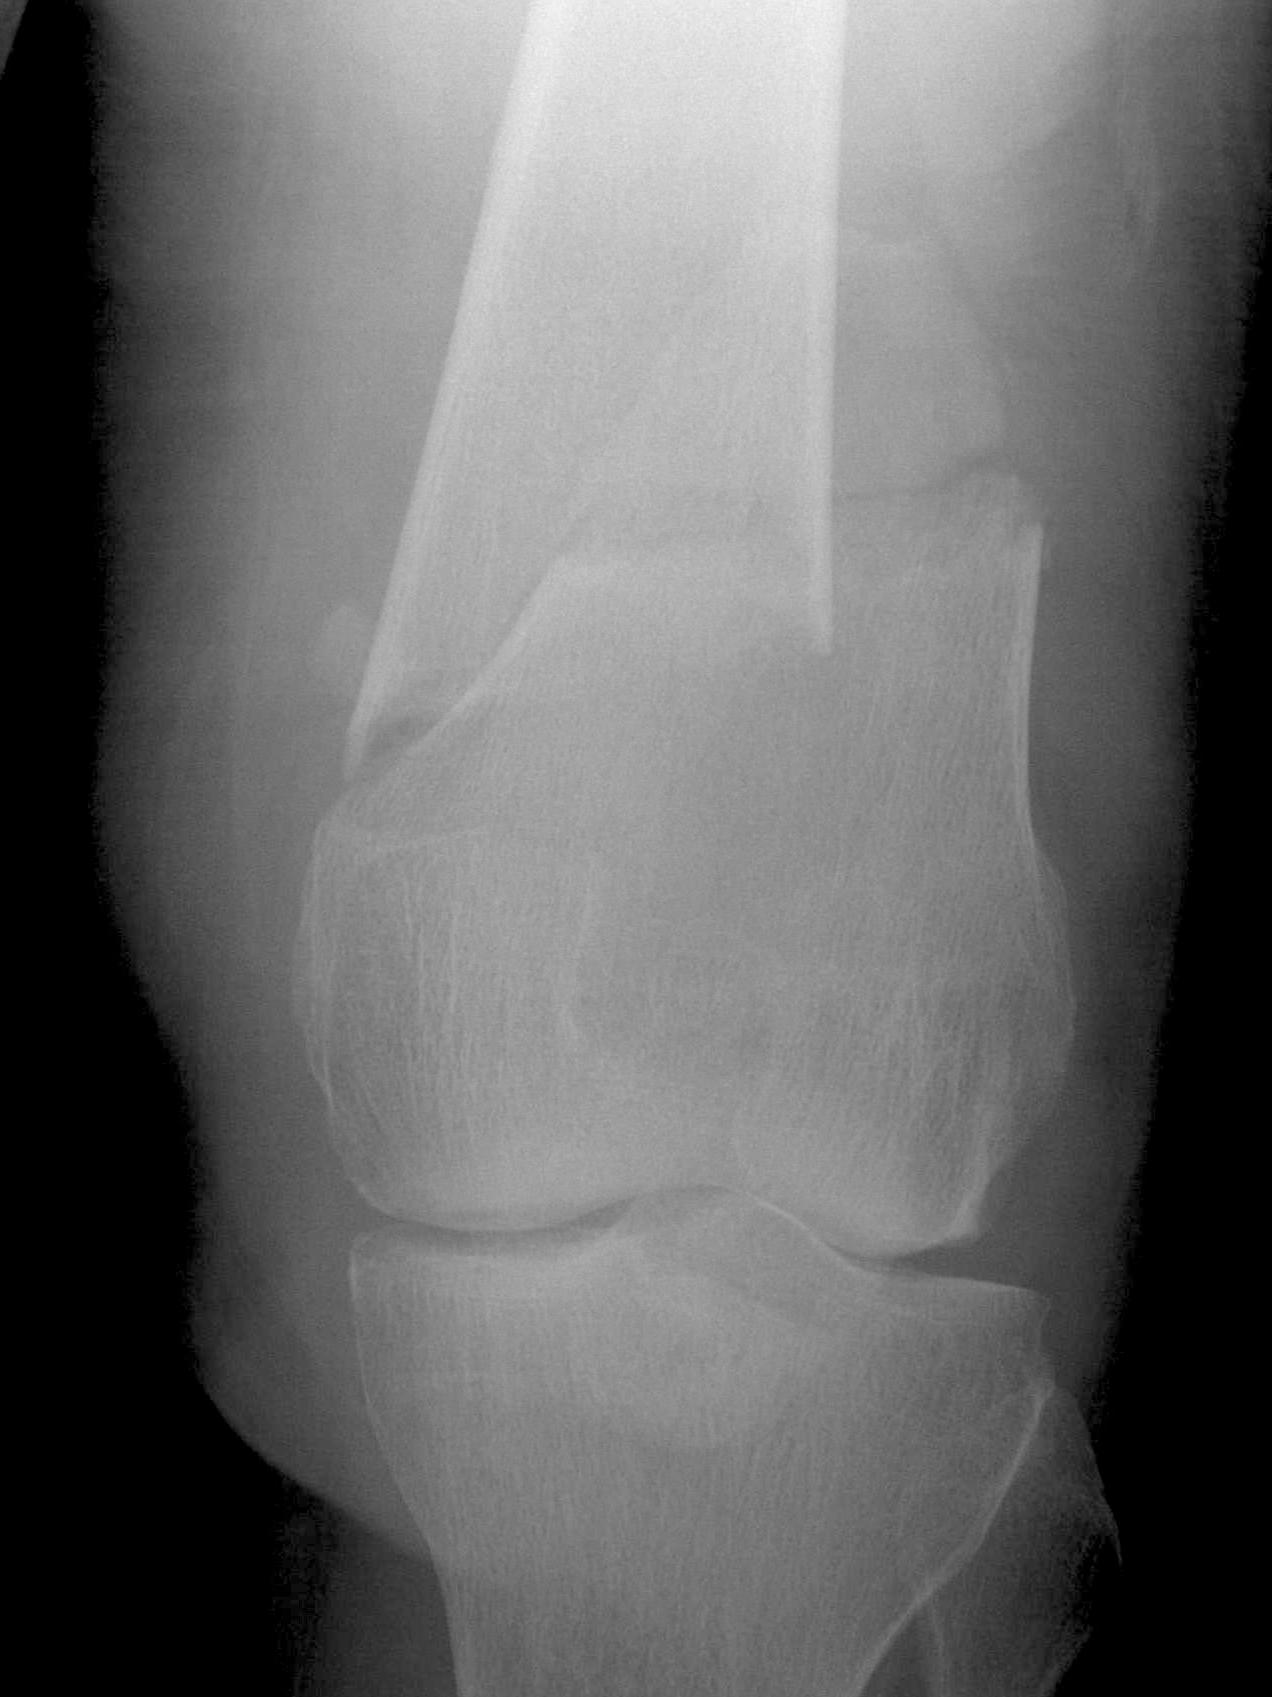

AO Type A: Supracondylar / Extra-condylar

Xray

Options

Lateral plate

Retrograde IM nail